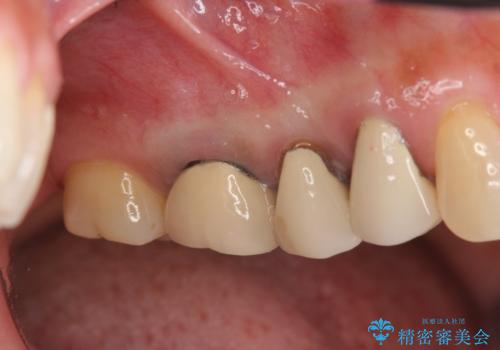

前歯の変色 セラミッククラウンによる審美回復

担当医 大元洋佑

神経をとった前歯が変色してきた